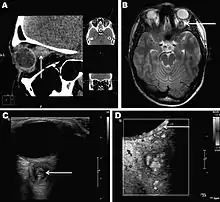

Infections in humans[3] usually manifest as a single subcutaneous nodule, which is caused by a macrofilaria that is trapped by the immune system. Subcutaneous migration of the worm may result in local swellings with changing localization. In addition, rare cases of organ manifestation have been reported, affecting the lung, male genitals, female breast, or the eye. The latter is found in particular during the migratory phase of the parasite. D. repens occurs more commonly in adults (aged 40–49 years). The only exception is in Sri Lanka, where children younger than nine years are most likely to be infected. The youngest individual reported was aged four months.[4]

Final diagnosis is established by microscopic examination of the excised worm. Making a definite species diagnosis on morphologic grounds is difficult, because a large number of zoonotic Dirofilaria species have been described that share morphologic features with D. repens.

- ↑ Sven Poppert, Maike Hodapp, Andreas Krueger, Guido Hegasy, Wolf-Dirk Niesen, Winfried V. Kern, and Egbert Tannich (November 2009). "Dirofilaria repens Infection and Concomitant Meningoencephalitis". Emerg. Infect. Dis. 15 (11): 1844–1846. doi:10.3201/eid1511.090936. PMC 2857255. PMID 19891881.